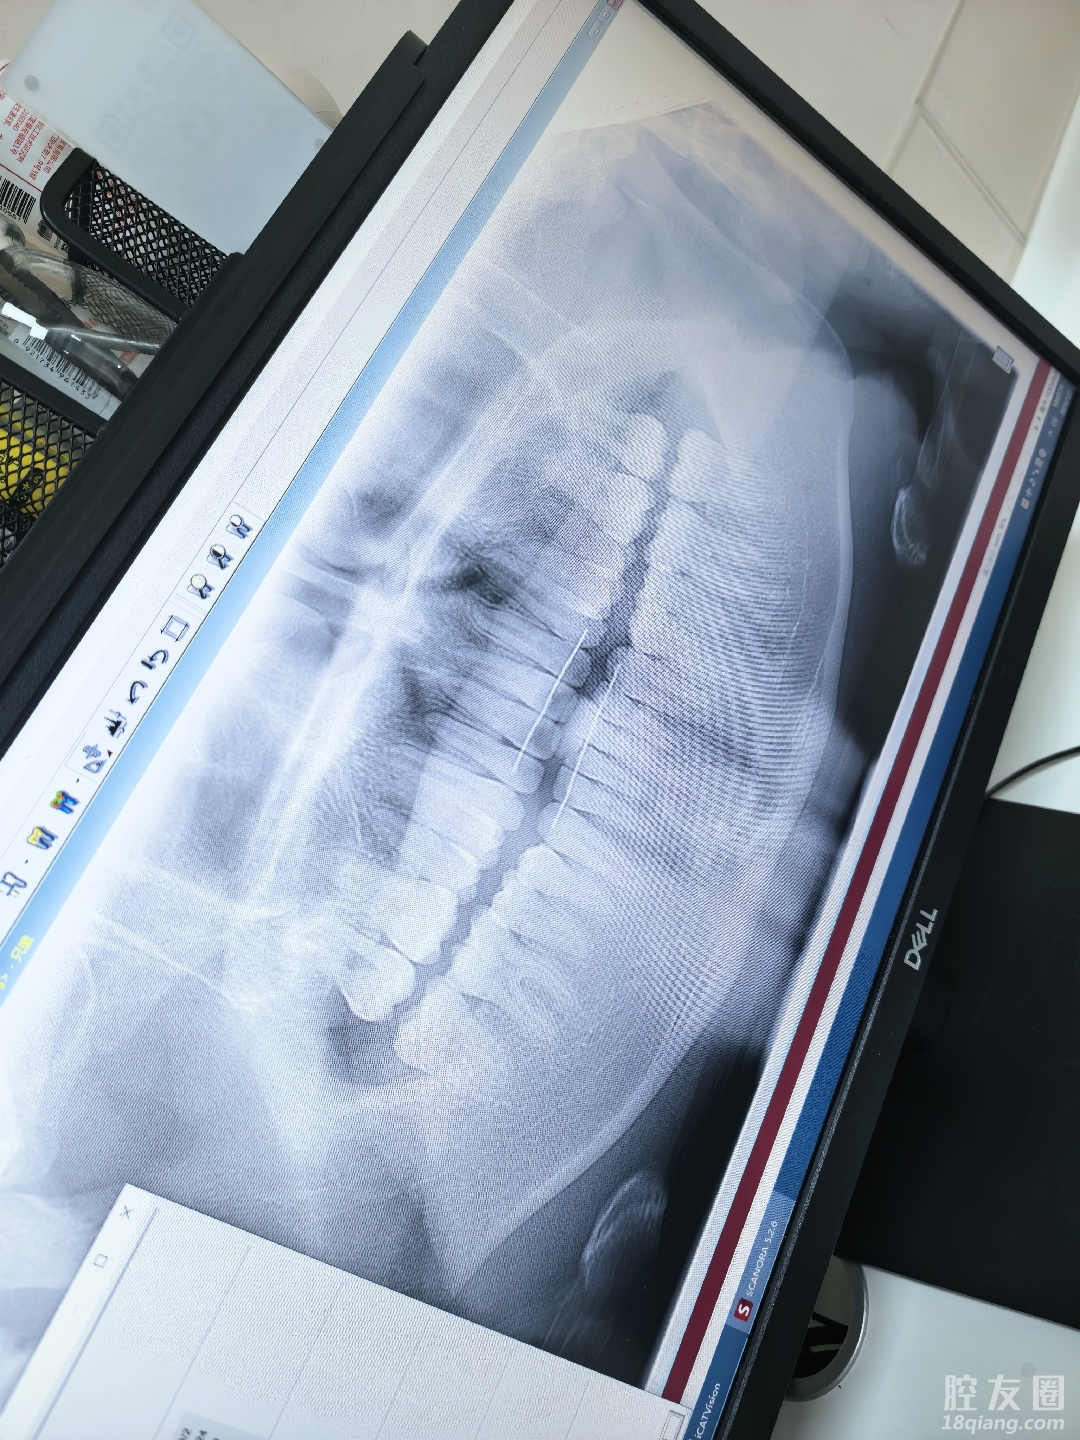

今天陪嫂子带着侄子把牙齿弄了,他小时候因为乳牙没去除就开始长恒牙,导致后来新牙斜着长了,原本也没太在意,一颗牙齿错位导致对称的牙齿也开始慢慢移位,最后整口牙都在偏移,他们就带他去做牙齿了

不过听矫正医生说的和医院给发了正畸前后图,感觉矫正牙齿还挺不错的,宜早不宜迟,现在不但前排牙齿矫正了,连后面的一整口都整齐了,孩子的脸袋也变规整了